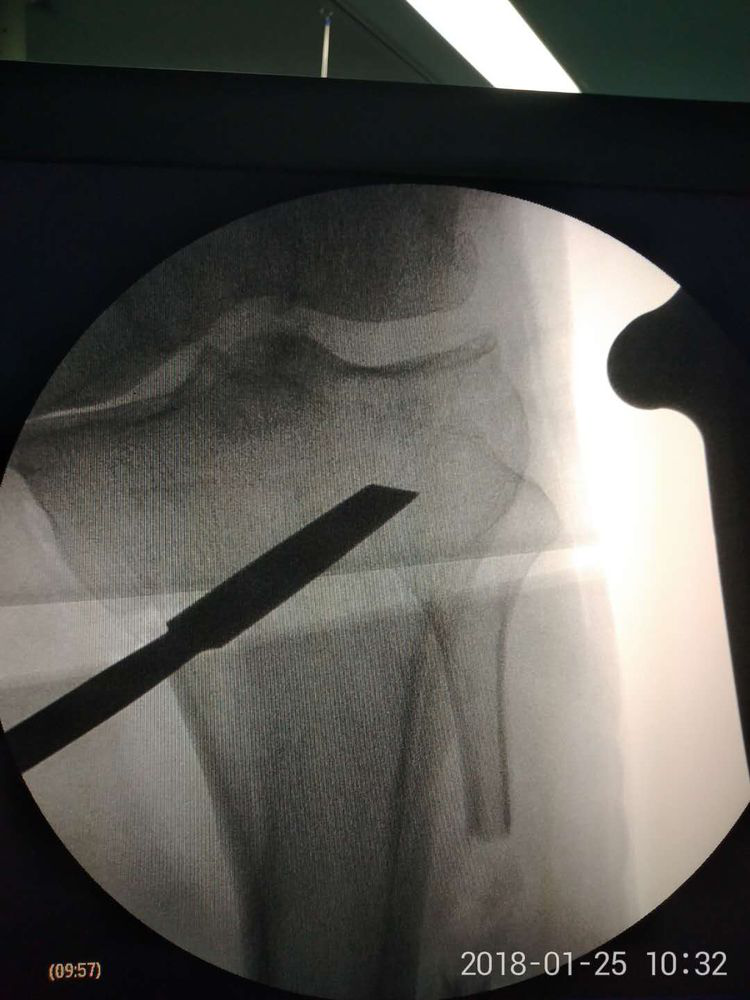

患者男,52歲,右膝關(guān)節(jié)疼痛、活動受限3年,加重1月。既往長期服用鎮(zhèn)痛藥物,近期關(guān)節(jié)腔內(nèi)注射玻璃酸鈉,膝關(guān)節(jié)疼痛癥狀進(jìn)行性加重,以致無法行走,患者為嚴(yán)重的膝關(guān)節(jié)內(nèi)翻畸形,保守治療無效,行膝關(guān)節(jié)置換術(shù)相對年齡較小,趙占富主任醫(yī)師決定采用"保膝"手術(shù)治療,膝關(guān)節(jié)內(nèi)外側(cè)切口均為4-5cm左右。

脛腓骨雙截骨平衡手術(shù)特點(diǎn):1、手術(shù)為微創(chuàng)手術(shù),創(chuàng)傷小,手術(shù)時(shí)間短,出血少,并發(fā)癥發(fā)生率低;2、脛骨近端為不全骨折,置入墊片后不影響下肢負(fù)重,可早期下地功能鍛煉;3、手術(shù)無需鈦板固定,費(fèi)用少;4、置入墊片為可吸收材料,無需取出,且不影響后期膝關(guān)節(jié)置換術(shù)。